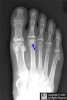

X-ray에서 골두의 편평화, 경화나 분절이 나타납니다.

X-ray : 프라이버그씨 병(Freiberg’s disease)